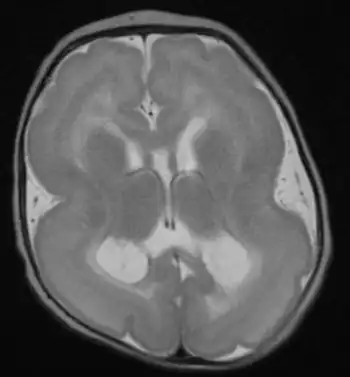

| Lissencephalic brain of a human, lacking surface convolutions (Gyrification) | |

Lissencephaly (/ˌlɪs.ɛnˈsɛf.əl.i/, meaning "smooth brain")[1] is a set of rare brain disorders where the whole or parts of the surface of the brain appear smooth.[2] It is caused by defective neuronal migration during the 12th to 24th weeks of gestation resulting in a lack of development of brain folds (gyri) and grooves (sulci).[3] It is a form of cephalic disorder. Terms such as agyria (no gyri) and pachygyria (broad gyri) are used to describe the appearance of the surface of the brain.